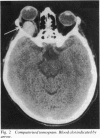

A 57-year-old housewife, with controlled hypertension, presented with acute right proptosis and visual loss with external ophthalmoplegia due to spontaneous orbital haemorrhage. Vision and ocular motility were returned to normal by the rapid surgical evacuation of the blood. Acute orbital haemorrhage is an ocular emergency requiring urgent treatment to prevent the usual previously reported outcome of permanent visual loss.